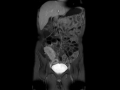

Crohn's disease

MRI images demonstrate extensive wall thickening and hyperenhancement of the terminal ileum, compatible with the patients known Crohns disease.